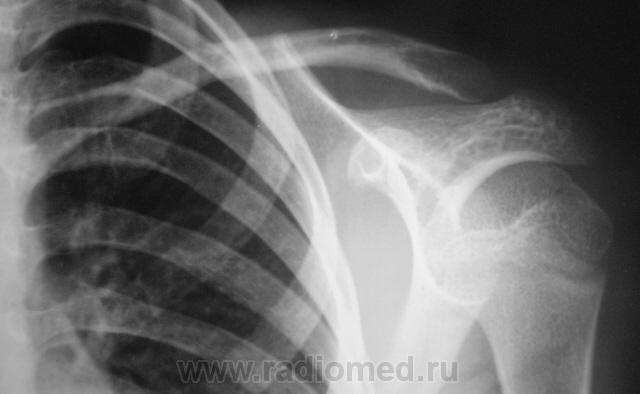

Пол пациента: Мужской пол Тип патологии: Травма Область исследования: Скелетно-мышечная система Методы исследования: Rg Травма. Пациент (ребенок) направлен хирургом на рентгенографию плечевого сустава. Ваше мнение уважаеиые коллеги? https://radiomed.ru/sites/default/files/styles/case_slider_image/public/user/12/2.Reb_.jpg?itok=SqZhLtB6 ID:208 Пт, 15/01/2010 - 13:23 #1 lupan Не на сайте Был на сайте: 6 лет 10 месяцев назад Зарегистрирован: 07.01.2010 - 17:17 Публикации: 1406 По-моему норма. Эпифизиолиз сомнителен. Великое преймущество врача заключается в том, что он не обязан следовать собственным советам. ( А. Кристи) Пт, 15/01/2010 - 14:53 #2 Ola-la Не на сайте Был на сайте: 10 месяцев 6 дней назад Зарегистрирован: 06.12.2008 - 09:33 Публикации: 1786 Эпифизеолиза нет. Есть сомнения по поводу взаимоотношений в суставе, но это думаю погрешности укладки. https://www.instagram.com/pediatricradiology/ Пт, 15/01/2010 - 15:32 #3 Катенёв Валенти... Не на сайте Был на сайте: 7 лет 2 недели назад Зарегистрирован: 22.03.2008 - 22:15 Публикации: 54876 А ключица, не внушает подозрений? Пт, 15/01/2010 - 15:39 #4 Ola-la Не на сайте Был на сайте: 10 месяцев 6 дней назад Зарегистрирован: 06.12.2008 - 09:33 Публикации: 1786 Нет, может раньше был перелом? https://www.instagram.com/pediatricradiology/ Пт, 15/01/2010 - 15:47 #5 Катенёв Валенти... Не на сайте Был на сайте: 7 лет 2 недели назад Зарегистрирован: 22.03.2008 - 22:15 Публикации: 54876 А мне, вот здесь подозрительно. Приложения: Пт, 15/01/2010 - 17:08 #6 lupan Не на сайте Был на сайте: 6 лет 10 месяцев назад Зарегистрирован: 07.01.2010 - 17:17 Публикации: 1406 Сомнительно как-то всё на экране. Великое преймущество врача заключается в том, что он не обязан следовать собственным советам. ( А. Кристи) Пт, 15/01/2010 - 18:23 #7 Катенёв Валенти... Не на сайте Был на сайте: 7 лет 2 недели назад Зарегистрирован: 22.03.2008 - 22:15 Публикации: 54876 "Сомнительно"? Приложения: Сб, 16/01/2010 - 12:30 #8 lupan Не на сайте Был на сайте: 6 лет 10 месяцев назад Зарегистрирован: 07.01.2010 - 17:17 Публикации: 1406 Да, перелом есть. Великое преймущество врача заключается в том, что он не обязан следовать собственным советам. ( А. Кристи)

По-моему норма. Эпифизиолиз сомнителен.

Эпифизеолиза нет. Есть сомнения по поводу взаимоотношений в суставе, но это думаю погрешности укладки.

А ключица, не внушает подозрений?

Нет, может раньше был перелом?

А мне, вот здесь подозрительно.

Сомнительно как-то всё на экране.

"Сомнительно"?

Да, перелом есть.